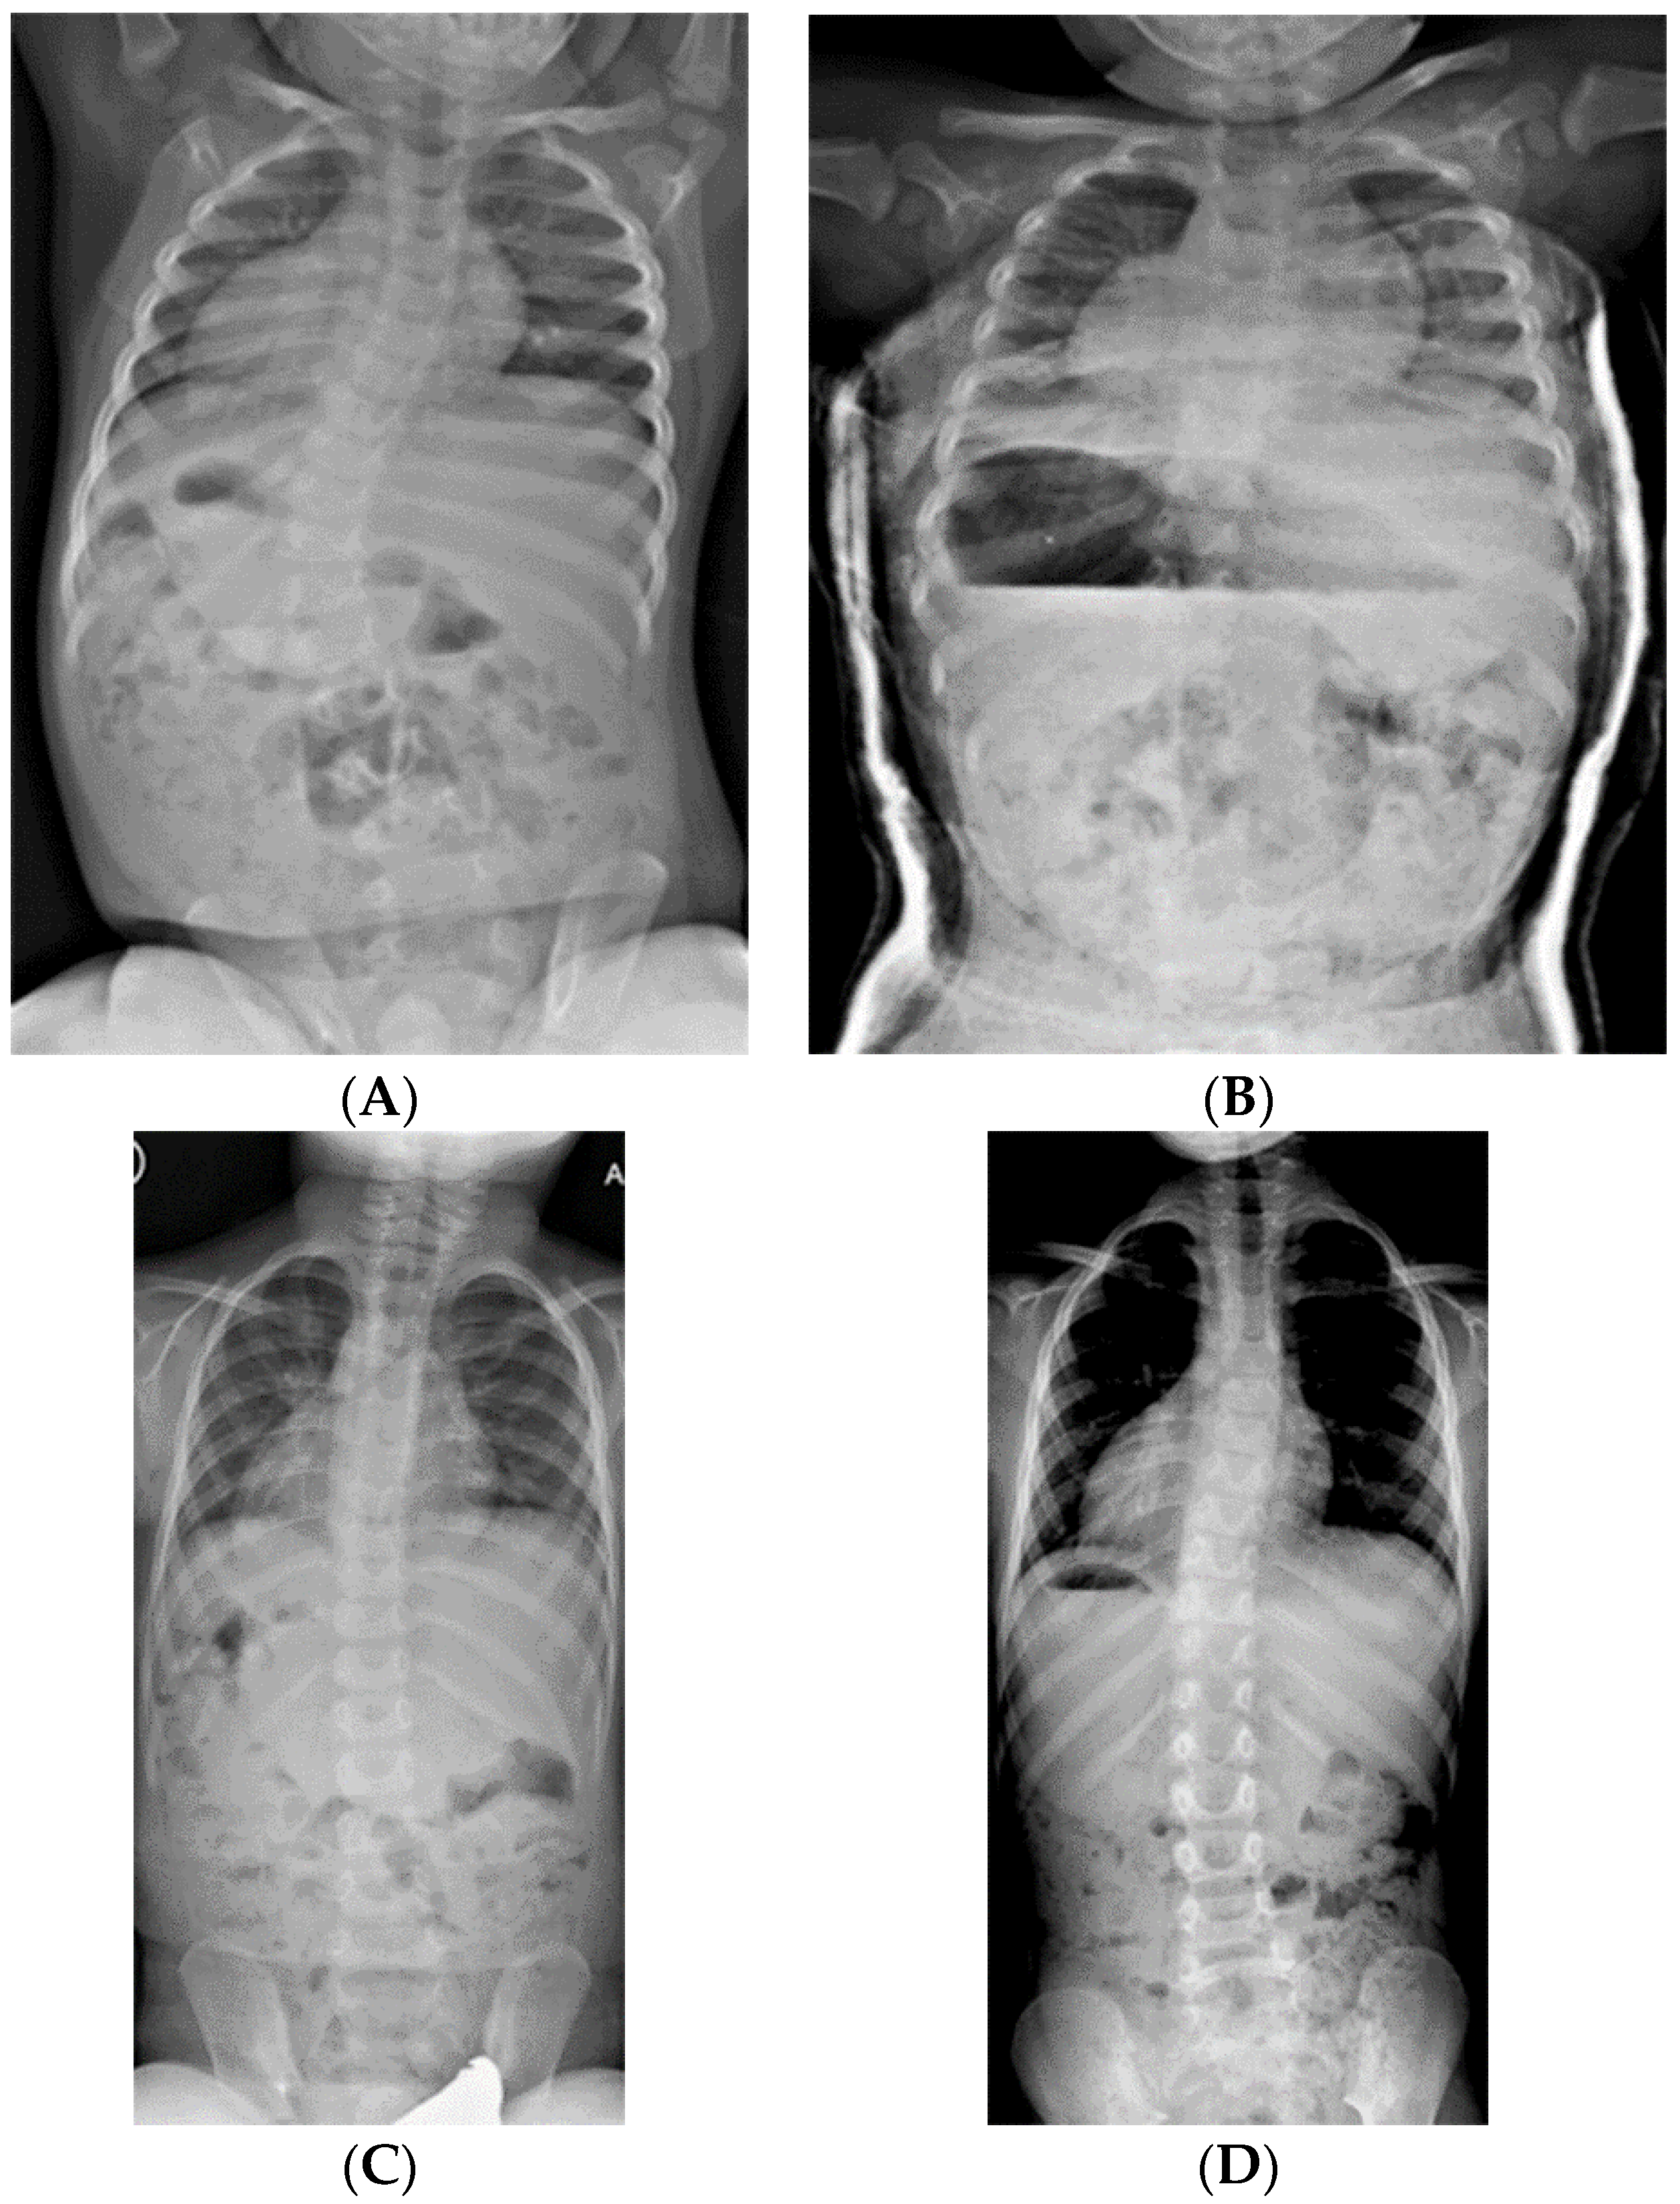

Although there is the occasional case where an infantile curve spontaneously resolves, most curves over 25° require treatment. If a curve would naturally correct without treatment, it will merely correct quicker with treatment. Therefore, treating all curves at 25° appears to improve chances of intervening at the best possible moment to help a curve resolve. Indications for starting spine casting is a curve greater than 25° in a child over sitting age and usually younger than 3 years of age; we have initiated spinal casting on the occasional child at nearly 5 years of age. In the rare case when a child has a large curve before they begin sitting independently, a semi-rigid spine brace is used to temporize until they are suitably developed physically to start casting. There are three possible outcomes from cast treatment. The best outcome (“cured”) is the curve that can be reduced to either <15° out-of-cast, or 3 successive out-of-cast measurements of <25°, in which case the patient is transitioned to a brace, then weaned out of the brace after one year (Figure 3). More moderate curves, once they plateau in casting, are also transitioned to a brace, with the expectation that the brace will be long-term treatment. Severe curves are casted until the child is old enough to undergo surgery for an expandable spine implant (5–8 years of age) (Figure 4).

Figure 3.

(A) 19-month-old male with PWS deletion type with 52° curve. (B) Same patient at 20 months old, sitting in his first spinal cast, 10° curve in cast. (C) Same patient at 35 months old, after completing 8 casts, 11° curve. (D) Same patient at 6 years old, 3 years out of cast and 2 years out of brace, with an 18° curve.

Figure 4.

(A) 18-month-old female with PWS deletion type with 106° curve. (B) Same patient at 18 months old, sitting in first cast, 54° curve. (C) AP and lateral views of spine at 6 years old, after 18 casts, 61° curve, just prior to surgery. (D) AP and lateral views of spine 4 months after placing magnetically actuated spine rods T3–L3. Curve was corrected to 30°, maintaining her pre-operative kyphosis. (E) AP and lateral views of spine at 10 years old, just prior replacement with new expandable rods. Due to adding on, curve measures 50°, which was addressed by including L4 in the construct.

Oore et al. reported the only published series of serial casting for children with PWS, noting a reduction of curve size in their ten patients, from 45° to 37° [40]. We reviewed our results from 34 children with PWS with more than 24 months’ follow-up after their initial spine cast. The average age at initial casting was 32 months (range 14–64 months) with an average of 8 casts (range 3–18). Twelve children (35%) were in the “cured” group; all were weaned out of brace at one year after completion of casting. Seven of these patients had maternal disomy 15, five had the 15q11-q13 deletion, and the average initial curve was 44° (range 27°–80°). Another 18 patients transitioned to long-term brace wear (10 with deletion, 7 with maternal disomy 15, and one having an imprinting defect). Their average initial curve of 55° (range 27°–84°) became 35° (16°–64°) at the end of casting and was 46° (27°–84°) at two years’ follow-up. Four patients with severe initial curves (54°, 84°, 95°, and 106°) were controlled in casts until they reached a sufficient age for surgery (average 56 months old). Overall, the odds ratio for “curing” an initial curve of <50° was nine times that of a curve >50° in this cohort.